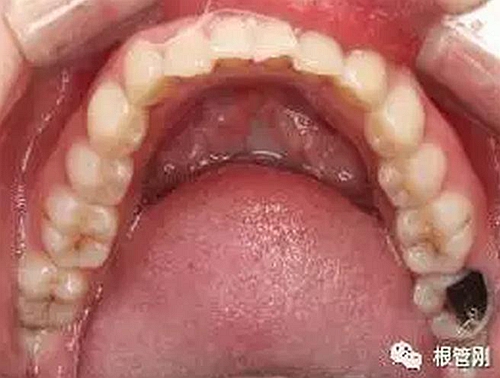

美學(xué)樹脂分層堆塑,還原本真!

10.jpg

深齲離牙髓炎僅一步之遙,也就意味著離根管治療僅一步之遙。于細(xì)微處見(jiàn)知著,于細(xì)小之處見(jiàn)技術(shù)!不管怎樣,除疾病,還健康,是我們的共同初心,盡醫(yī)生所能,也盡患者所能,方能得始終!